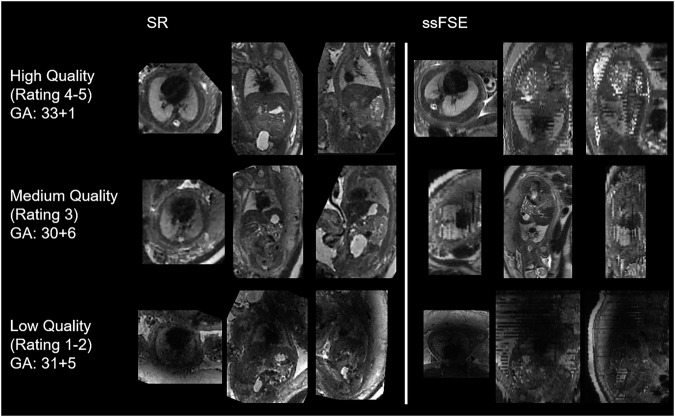

Materials and methods: In this single-center retrospective study, fetal lung volumes calculated from both SR reconstructions and the original images were analyzed. Three radiologists manually segmented the fetal lungs and rated the image quality of all images and reconstructions. Fetal lung volumes were calculated, and the coefficient of variation (CV) was determined for each set of images. Bland-Altman plots were generated, and intraclass correlation coefficients (ICCs) were calculated. A one-sided paired Wilcoxon test was used to compare the fetal lung volume CVs, and a two-sided paired t-test was used to compare the lung volumes. The quality ratings were compared using a two-sided paired Wilcoxon test.

Results: A total of 98 fetal scans with gestational ages from 19 to 37 weeks were evaluated. There was a significantly lower CV in the lung volumes segmented from the SR reconstructions (p < 0.001), and the ICCs of the reconstructions were higher than those determined from the original images. Bland-Altman plots demonstrated better agreement in the SR reconstruction lung volumes. No significant differences in quality ratings or lung volumes were found.